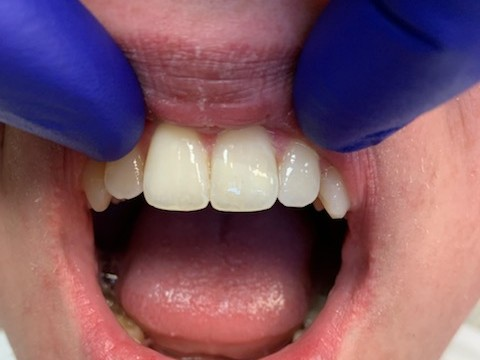

DentXpinTM – placed April, 12, 2012 and still holding strong.

1

DentXpinTM repair.